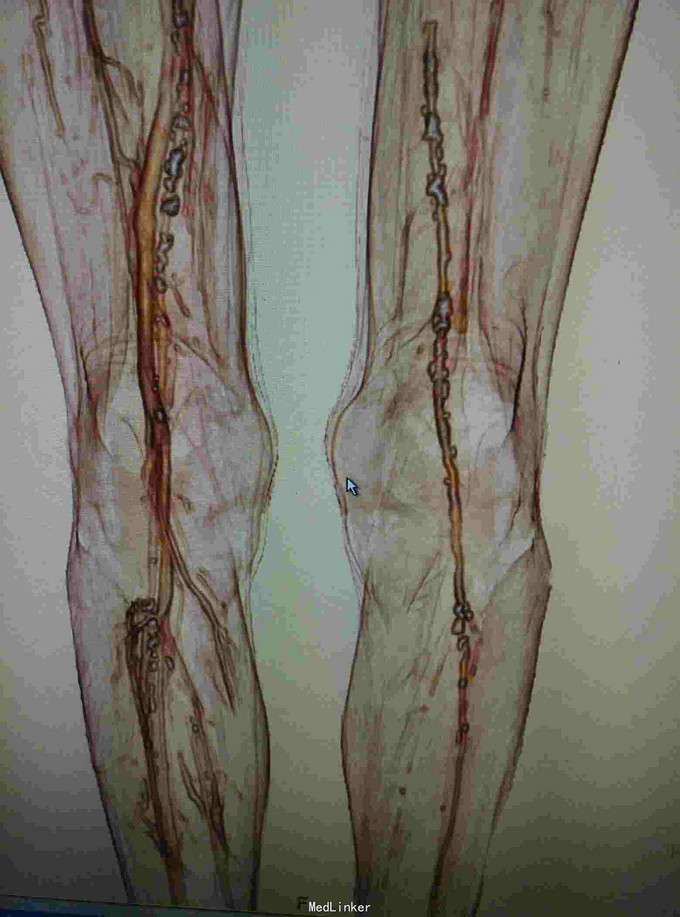

左下肢皮温降低,左足背可见紫红色淤斑,左股动脉扪及微弱波动。下肢血管成像提示:双下肢动脉节段性不同程度狭窄、闭塞。

双下肢动脉硬化闭塞症 手术:左侧髂动脉探查术,术中探查股动脉,导丝导管尝试通过闭塞段髂动脉,但反复尝试无法继续。右侧也无法通过。家属放弃。

ASO是动脉粥样硬化引起的,好发于45岁以上男性,早期主要表现为间歇性跛行,晚起出现静息痛、缺血坏跙或溃疡。动脉造影有助于确定诊断,临床上可采用PTA,内膜剥脱术、旁路转流术等。